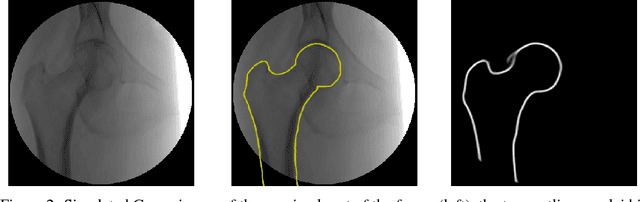

We propose approaches based on deep learning to localize objects in images when only a small training dataset is available and the images have low quality. That applies to many problems in medical image processing, and in particular to the analysis of fluoroscopic (low-dose) X-ray images, where the images have low contrast. We solve the problem by incorporating high-level information about the objects, which could be a simple geometrical model, like a circular outline, or a more complex statistical model. A simple geometrical representation can sufficiently describe some objects and only requires minimal labeling. Statistical shape models can be used to represent more complex objects. We propose computationally efficient two-stage approaches, which we call deep morphing, for both representations by fitting the representation to the output of a deep segmentation network.